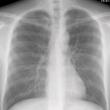

RGP,巩膜镜(大号RGP),少看手机不要揉眼